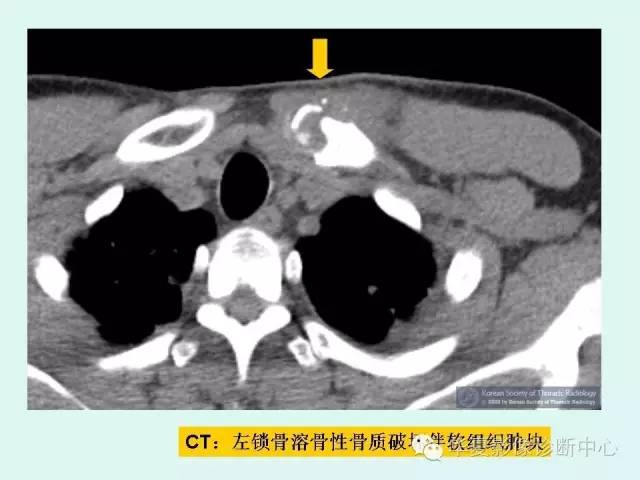

肺转移瘤的十种不典型CT表现